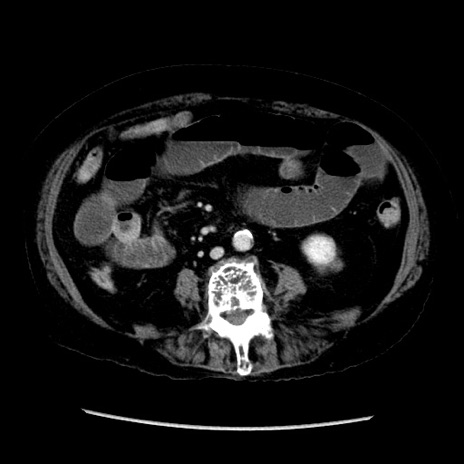

症例14(横断像)

【症例】 90歳代女性

【主訴】 腹痛・嘔吐

【現病歴】今朝から左側腹部痛を認めた。 経過観察していたが、嘔吐を認めたため来院。

【既往歴】 子宮癌術後

【身体所見】 意識清明、BP 127/54mmHg、P 98bpm Sp02 95%(RA)、BT 35.8°C、腹部平坦・軟腸ぜん動音聴取良好、右下腹部圧痛(+) 反跳痛なし

【データ】WBC 9800、CRP 0.46